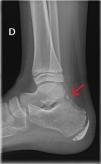

We present the case of a boy aged 11 years assessed for pain located in the right ankle of three days’ duration in absence of previous trauma. The patient reported playing soccer sometimes. He described pain at the site of insertion of the Achilles tendon, with shooting pain reproducible on walking. The patient had no pain or inflammation elsewhere. The physical examination was unremarkable. An X-ray of the ankle (Fig. 1) revealed the presence of an extra bone (os trigonum).

Os trigonum is an accessory bone present from birth in 14% of 25% of individuals, unilaterally or bilaterally, located behind the talus and connected to it through a fibrous band.